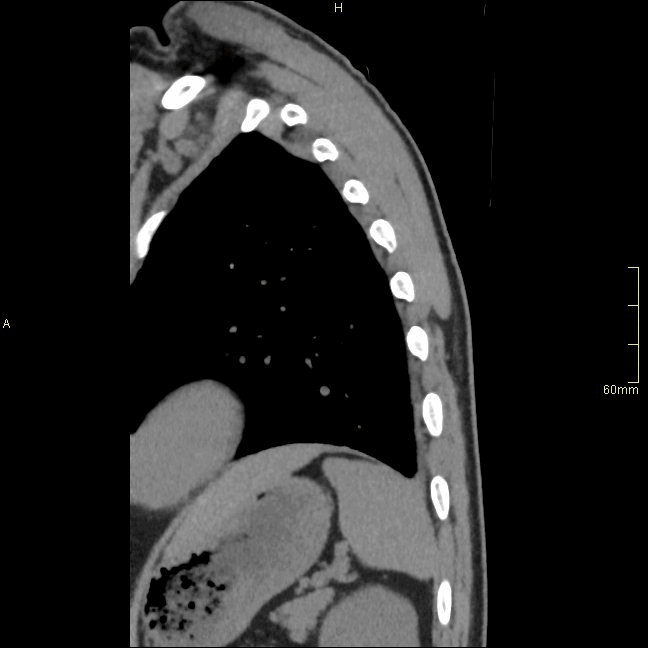

CT Thoracic Spine Non Contrast- Bone window (sagittal)

CT Thoracic Spine Non Contrast- Soft Tissue window (sagittal)